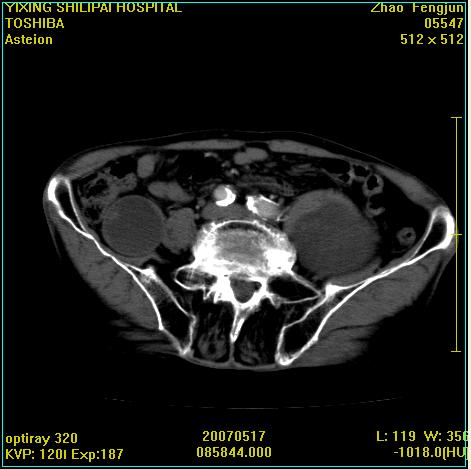

考虑:1、左侧腰大肌囊实性占位性病变(囊性神经根鞘瘤?);

2、右侧兰尾区囊性占位性病变(兰尾囊肿?囊腺癌?类癌?)

以下是引用xiaoniu在2007-5-26 10:45:00的发言:[br]腰大肌的病变应该没有问题,增强扫描还有轻度强化及细小血管影入内,应该排除脓肿,考虑占位性病变,腰大肌的占位多考虑:神经源性肿瘤。另外腹主动脉下端有真假腔的强化,考虑:主动脉夹层。[br][br][本贴已被 xiaoniu 于 2007-5-26 10:46:39 修改过]

以下是引用老爱克斯新网客在2007-5-26 18:26:00的发言:[br]1左下腹囊实性占位肿块,增强后不均匀强化,位于脊柱旁,椎体骨质无破坏软组织无肿胀,考虑神经源肿瘤神经鞘瘤可能大,2右下腹囊性占位性病变,增强后囊壁强化,考虑阑尾囊肿或囊腺瘤,